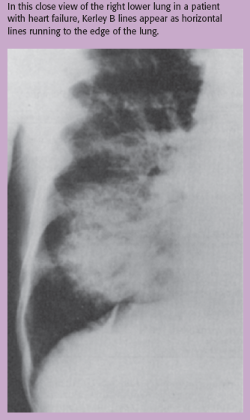

Kerley B lines can also be seen on a CXR in a patient with pulmonary edema. (See Kerley B lines.) These are thin, horizontal lines of fluid, no more than 2 cm long, which can be seen in the lung periphery near the costrophrenic angles and lateral wall.2

Figure. Kerley B lin... - Click to enlarge in new windowFigure. Kerley B lines